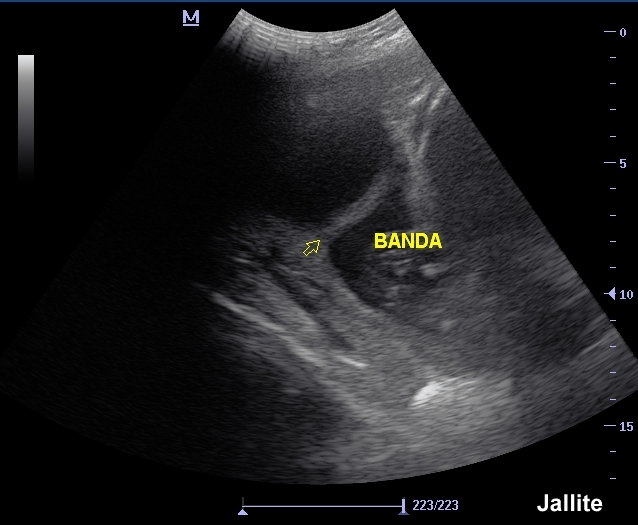

Early pregnancy with amniotic bands. USG Ultrasound YouTube Is Amniotic Band Dangerous In other instances, a band can be wrapped around a limb (arm or leg) resulting in. Amniotic band syndrome will have bands on more than one part of the body. Overall, amniotic bands have been reported in up to 1 in 1200 live births. Amniotic bands attached to the face or neck can sometimes cause deformities such as cleft lip. Is Amniotic Band Dangerous.